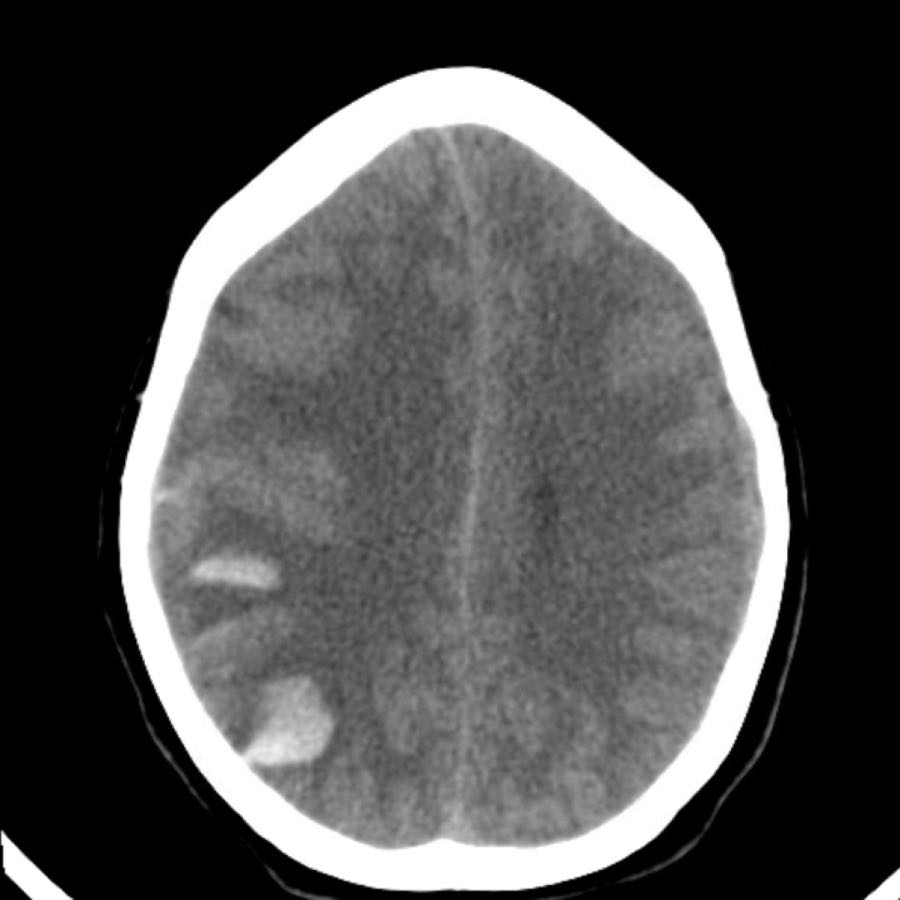

Ba hình ảnh đầu tiên cho thấy khối tụ máu lớn tại hạch nền bên phải kèm phù não lan rộng.

Hình ảnh theo dõi một năm sau cho thấy hình ảnh hang hóa dạng tuyến tính do mất mô (mũi tên) và giảm tỷ trọng hạch nền là hậu quả của xơ hóa thần kinh đệm (gliosis).